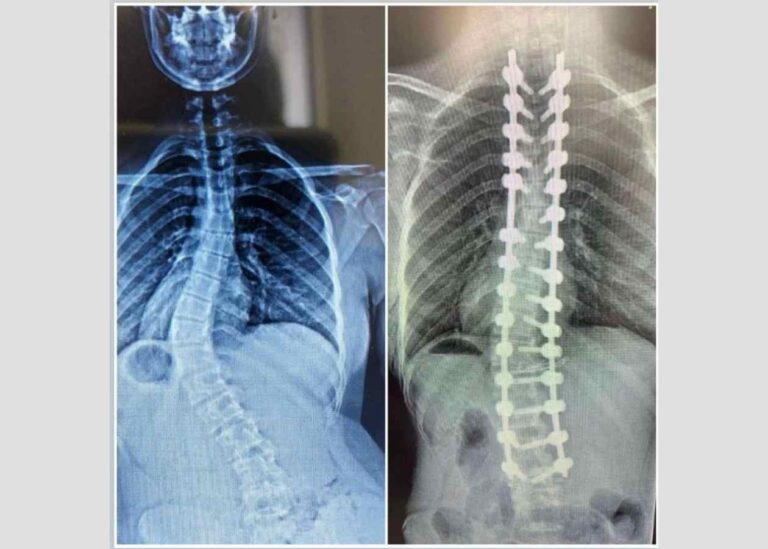

Omurga sağlığı, vücudun hareket kabiliyetini ve yaşam kalitesini doğrudan etkileyen temel unsurdur. Skolyoz, yani omurganın yana…